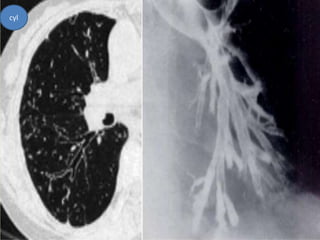

cyl

 “Tramlines” or “honeycombing” represents

dilated, thickened bronchial walls.

 Bronchial dilation, the cardinal sign of

bronchiectasis, is characterised on HRCT by a

bronchoarterial ratio (BAR) of .1, lack of

bronchial tapering, and visibility of airways

within 1 cm of the pleural surface or abutting

the mediastinal pleural surface.